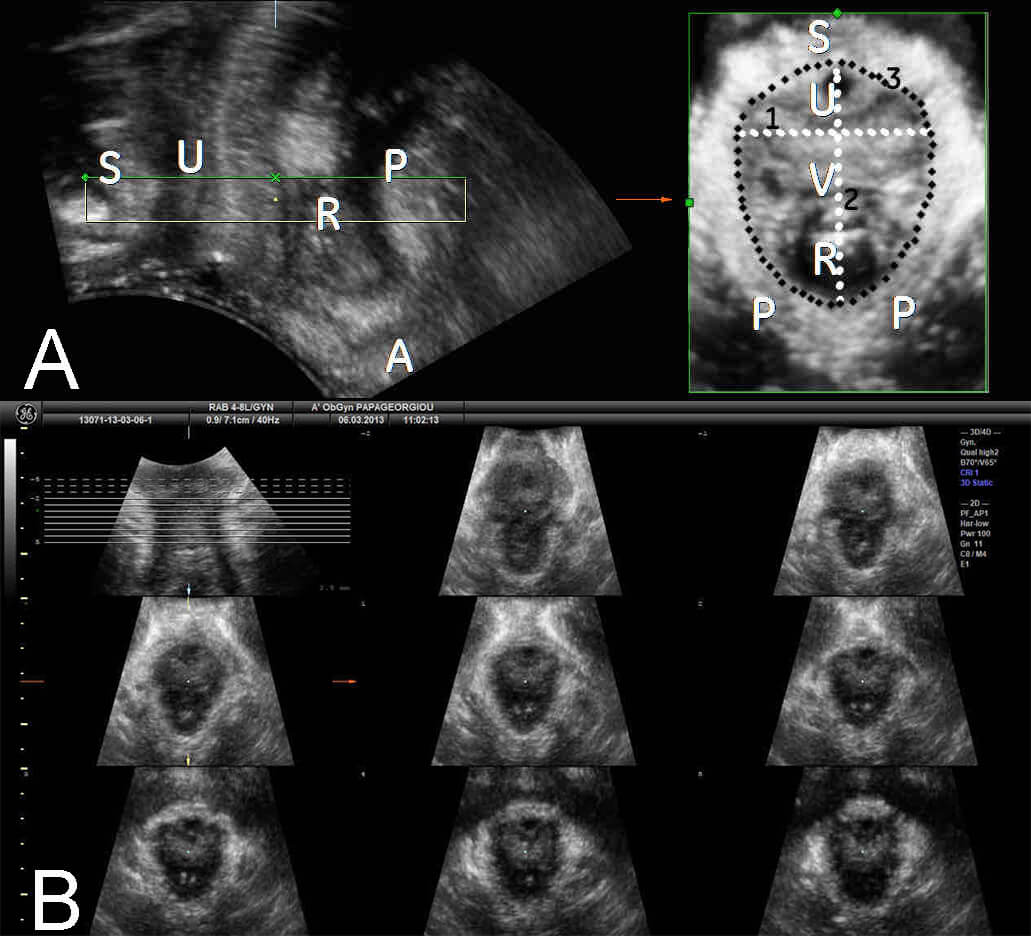

Fig. 2.

Three-dimensional transperineal ultrasound (3D-TPUS) imaging of the levator hiatus. (A) 3D-TPUS imaging of minimal dimensions of the levator hiatus during PFMC at the saggital plane (left), and reconstruction at the axial plane (right). (B) Tomographic ultrasound image (TUI) of the minimal dimensions of the levator hiatus during PFMC. PFMC, pelvic floor muscle contraction; S, symphysis pubis; U, urethra; R, rectum; P, puborectalis muscle; A, anus; V, vagina; 1, left-right diameter; 2, anterior-posterior diameter; 3, hiatal circumference.